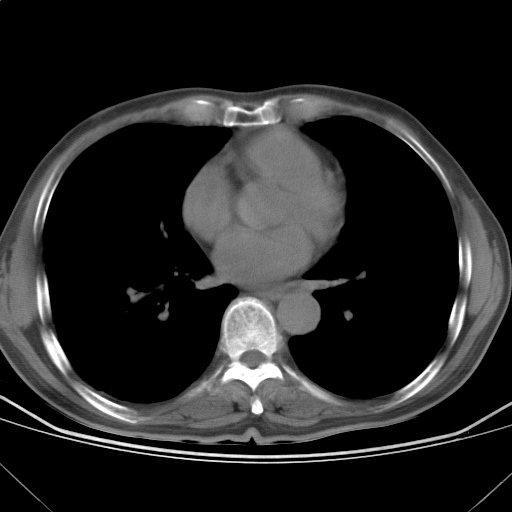

以下是引用随光逐影在2009-5-1 13:53:00的发言:[br]考虑为:1)两肺血行播散型肺结核;2)右肺下叶炎症感染。3)右侧胸膜增厚。